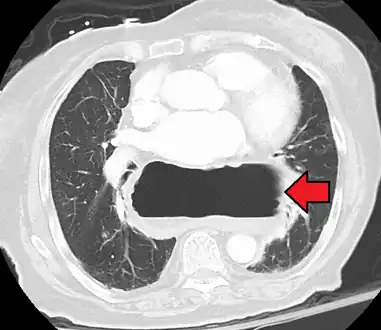

The diagnosis of a hiatal hernia is typically made through an upper GI series, endoscopy, high resolution manometry, esophageal pH monitoring, and computed tomography (CT). Barium swallow as in upper GI series allows the size, location, stricture, stenosis of oesophagus to be seen. It can also evaluate the oesophageal movements. Endoscopy can analyse the esophageal internal surface for erosions, ulcers, and tumours. Meanwhile, manometry can determine the integrity of esophageal movements, and the presence of esophageal achalasia. pH testings allows the quantitative analysis of acid reflux episodes. CT scan is useful in diagnosing complications of hiatal hernia such as gastric volvulus, perforation, pneumoperitoneum, and pneumomediastinum.[8]